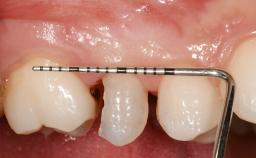

This 41-year-old female patient was referred to the clinic for the replacement of the right central incisor, since the tooth had developed a root fracture in the long axis that made extraction necessary. The healthy, non-smoking patient was first seen with the tooth still in place. A detailed Esthetic Risk Assessment was performed.The patient was worried about her dental esthetics and had high expectations for a successful treatment outcome from an esthetic point of view. The patient had a medium lip line that displayed parts of the gingiva in the anterior maxilla upon smile.